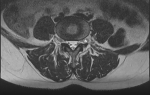

- Рентген.

- КТ.

- Миелографию или МРТ.

- Неврологический осмотр.

Только после проведения данных процедур врач сможет поставить точный диагноз и выявить степень повреждения.